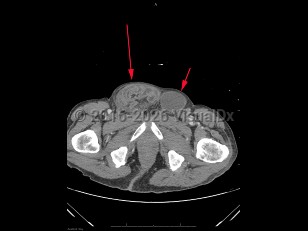

An inguinal hernia is a protrusion of an intraabdominal organ, often the small bowel, through an opening in the inguinal area of the abdominal wall. Inguinal hernias are very common, occurring in approximately 5% of the general population. Risk factors include a personal / family history of hernias, history of prior hernia or hernia repair, advanced age, male sex, smoking, prior abdominal wall injury, chronic constipation, and chronic cough. Inguinal hernias can be congenital or acquired. They are caused by a weakening or failed closure of fibromuscular groin tissue.

Inguinal hernias can be classified as either direct or indirect, determined by their location. An indirect inguinal hernia's defect is at the internal inguinal ring. A direct inguinal hernia's defect is medial to the inferior epigastric vessels within Hesselbach's triangle. Indirect inguinal hernias are more common and are often attributed to congenital defects; direct inguinal hernias are often acquired in the setting of connective tissue weaknesses.